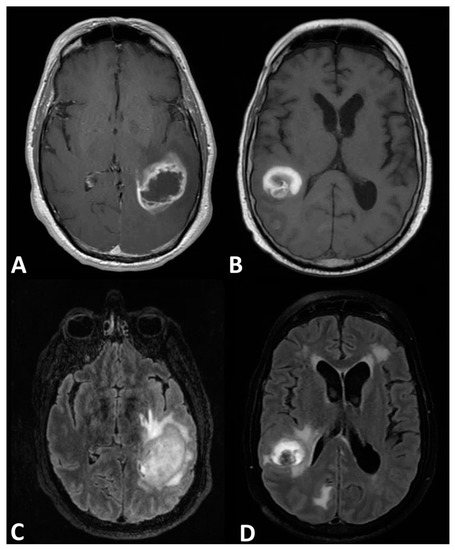

2. Magnetic Resonance Imaging

4.1. Diffusion-Weighted Imaging—Measurement of Apparent Diffusion Coefficient